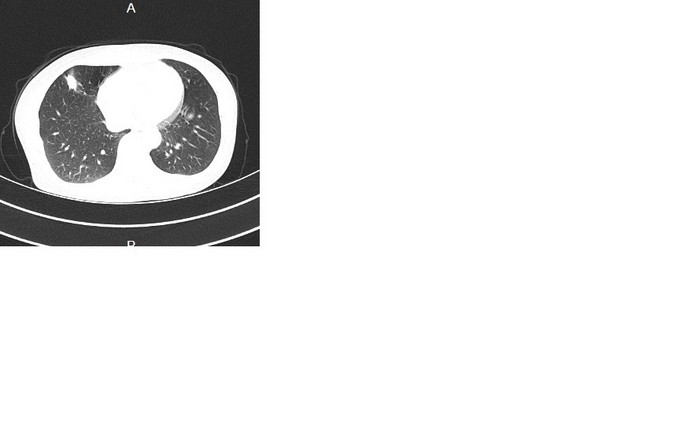

辅助检查:2015.7.31胸部CT(196593):右肺中叶炎症,右肺上叶多发肺大泡。2015.9.10胸部CT(200837):右肺中叶高密度灶,建议增强扫描;右肺上叶肺大泡。2015.9.16胸部增强CT:右肺中叶外侧段结节,恶性不除外,建议随访复查。右上肺肺气囊。右侧第5肋骨致密影。附见:肝脏膈面海绵状血管瘤考虑;肝脏囊肿。2015.9.11血常规:未见明显异常。入院后检查:09月19日心电图:窦性心律;正常范围心电图。09月19日超声:心脏:三尖瓣轻度返流,右侧甲状腺结节伴钙化,双侧颈动脉局部内膜增厚伴左侧斑块。09月19日 总IgE测定+降钙素原定量检测:免疫球蛋白E104.90IU/ml。09月19日 甲功全套+肿瘤系列(女7项)+生化分析(病房):肌酸激酶184IU/L,乳酸脱氢酶316IU/L,血管紧张素转化酶10IU/L,胆固醇6.15mmol/L,抗甲状腺球蛋白抗体77.76U/ml,铁蛋白304.0ng/ml,同型半胱氨酸17.97μmol/L,肾小球滤过率估值1121.17ml/(min*1.73m^2。09月21日 尿常规:尿潜血2+,结晶+个/LP,白细胞酶1+。09月19日 BNP、血液常规/HCRP、结核杆菌抗体、红细胞沉降率测定ESR、活化CD4细胞+活化CD8细胞+淋巴细胞亚群(T/B/NK、血流变、血凝/D二聚体、肿瘤系列(6项)、大便常规隐血、过敏源/IgE、呼吸道核酸检测、抗核抗体测定(ANA)+ENA谱+ANCA、荧光法病原体抗体:未见异常。09月22日咽拭子一般细菌/真菌/嗜血菌:未培养出嗜血杆菌,正常菌群,未培养出真菌。09月23日痰结核菌涂片:未找到抗酸杆菌。09月24日痰一般细菌/真菌/嗜血菌:未培养出真菌,未培养出嗜血杆菌,正常菌群。09月23日气管镜各级支气管通畅,刷片:(气管镜刷片)未见肿瘤细胞。灌洗液抗酸杆菌阴性,09月23日针吸涂片:(收到针吸涂片)未见肿瘤细胞。09月25日右肺结节:(右肺穿刺活检组织)肉芽肿性炎,倾向结核。

根据病理结果,诊断肺结核,转结核科治疗。 肺部孤立性结节的知识点就不贴了,大家都很了解了。下面说说自己的体会,看到病理结果我的心中是一万只草泥马飞过,这不符合预期啊。 本病例胸部CT一直提示恶性,孤立性结节,形状不规则,大于1cm,有毛刺,有中央钙化,有明显强化,不太符合结核的好发部位,也不符合结核的多病灶,多堆聚,多钙化,少肿块,少增强的特点,所以一直当恶性肿瘤来看待,对临床有一定的误导。经验是看胸部CT还是要再认真仔细点,多考虑不典型表现,多学习各种肿块的特点,多考虑各种可能,少点盲目自信。